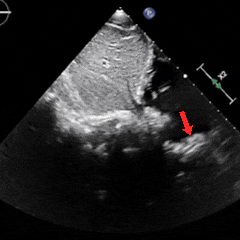

冠状动脉CTA:冠状动脉分布呈均衡型,左前降支中段浅肌桥;余冠状动脉CTA未见明显异常;卵圆孔未闭;左房囊袋。

冠脉CTA(长隧道+大开口+左房囊袋PFO)